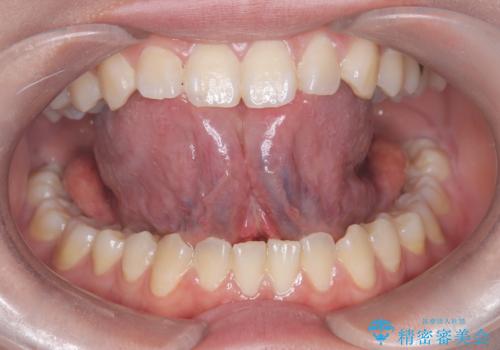

治療後、舌の可動域がかなり広がり患者様に大変ご満足していただけました。